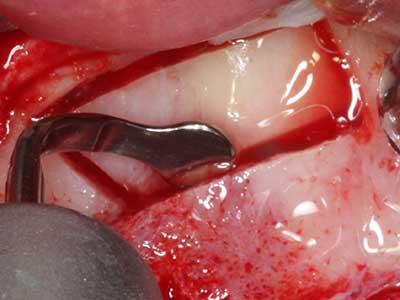

Indication: Preparation near nerves

As noted above, indications for piezosurgery can also be found in the field of conservative dental surgery. Special working tips simplify the exposure of root tips and make it easier to protect nerves and sinus mucous membranes, particularly in the lower premolar and upper posterior tooth regions. Angled diamond tips are used to precisely prepare the resection cavity for the retrograde root filler material for unsealed apical obturation. The ultrasonic technology means the tips can be very slender, which improves the view and the size of the access cavity. As a result, the application of ultrasonic surgery for this indication is one of the standard procedures for apical resection (Del Fabbro, Tsesis et al. 2010, Scarano, Artese et al. 2012).

Indication: Apical resection

When surgical procedures are performed on bone in the immediate vicinity of sensitive structures such as blood vessels or nerves, rotary instruments pose a significant risk of iatrogenic injury. Piezoelectric devices can be helpful for preparation of bone covers and removal of hard tissue close to nerves, particularly for exposure of nerves after iatrogenic injury but also during nerve lateralization for resective and reconstructive procedures or implant placement (Fig. 17-20). Light contact between the piezotip and the nerve does not generally result in damage but proceeding incautiously with saw-like motions or attachments where a residual bone substrate remains may cause temporary or even permanent nerve damage. However, the risk of damage is considered to be substantially lower than when using saws or milling instruments (Pereira, Gealh et al. 2014).